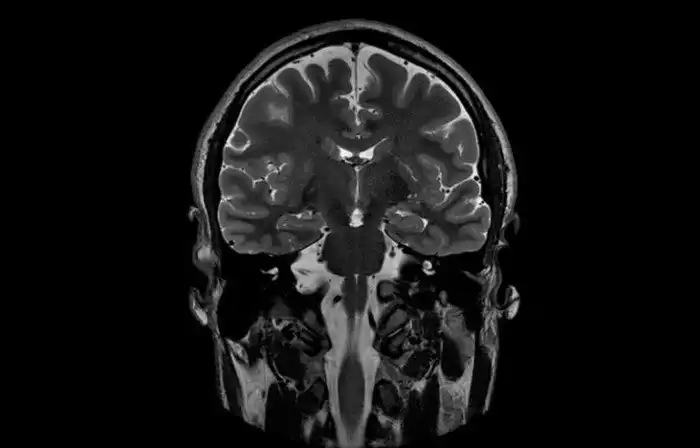

33-летняя пациентка психотерапевтической клиники в Германии ослепла в 13 лет. Женщина страдала от диссоциативного расстройства личности — в ней уживалось свыше 10 личностей. Примечательно, что спустя 20 лет некоторые из её личностей стали снова видеть. Слепыми остались только две личности. Энцифалограма мозга показала, что пациентка не лжёт: если текущая личность была слепа, то мозг не демонстрировал электрическую активность на визуальные стимулы, и наоборот.